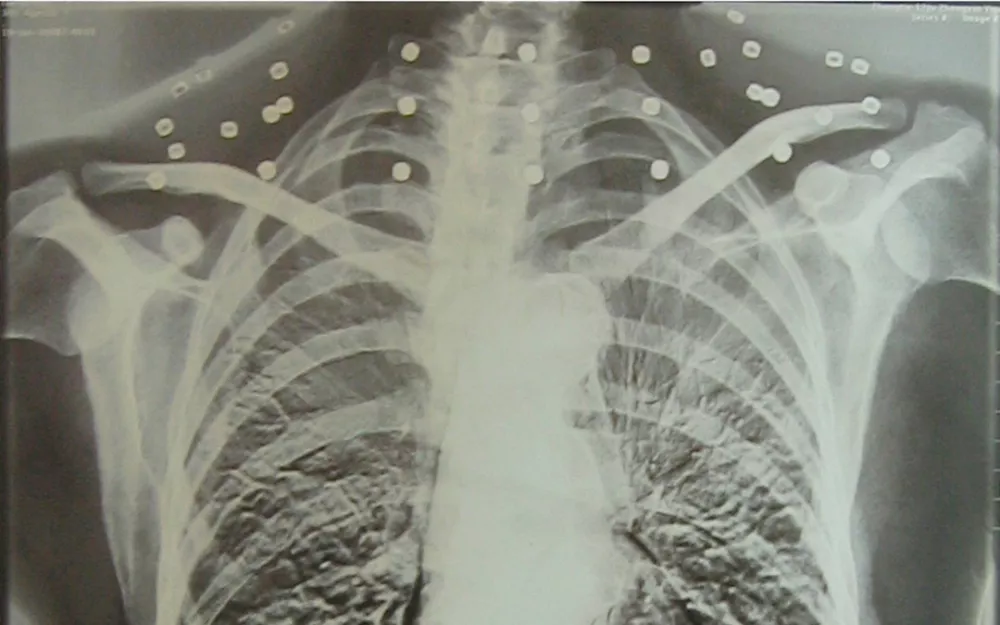

这张照片

是今年82岁的吴以先老人

拍摄的一张CT照

但实际上是

吴以先的颈部和腹部

共分布着33枚弹片

但是打进身体里的弹片

一直留在了体内

他体内的弹片都没有取出

但吴以先不考虑取出弹片

在他看来

这是他与战友并肩作战的见证

是他的勋章